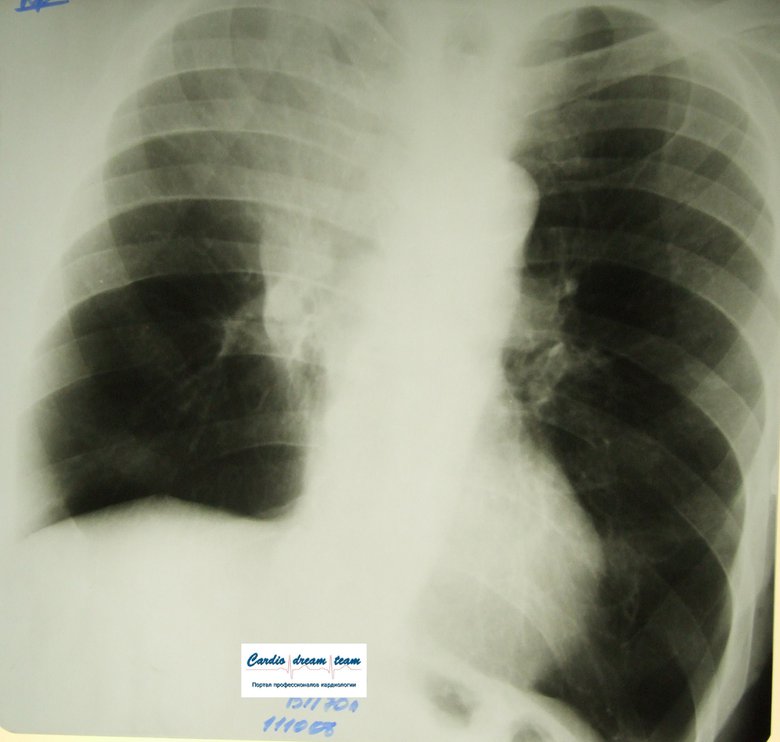

Центральный рак легкого

Обсуждали здесь viewtopic.php?f=24&t=2663